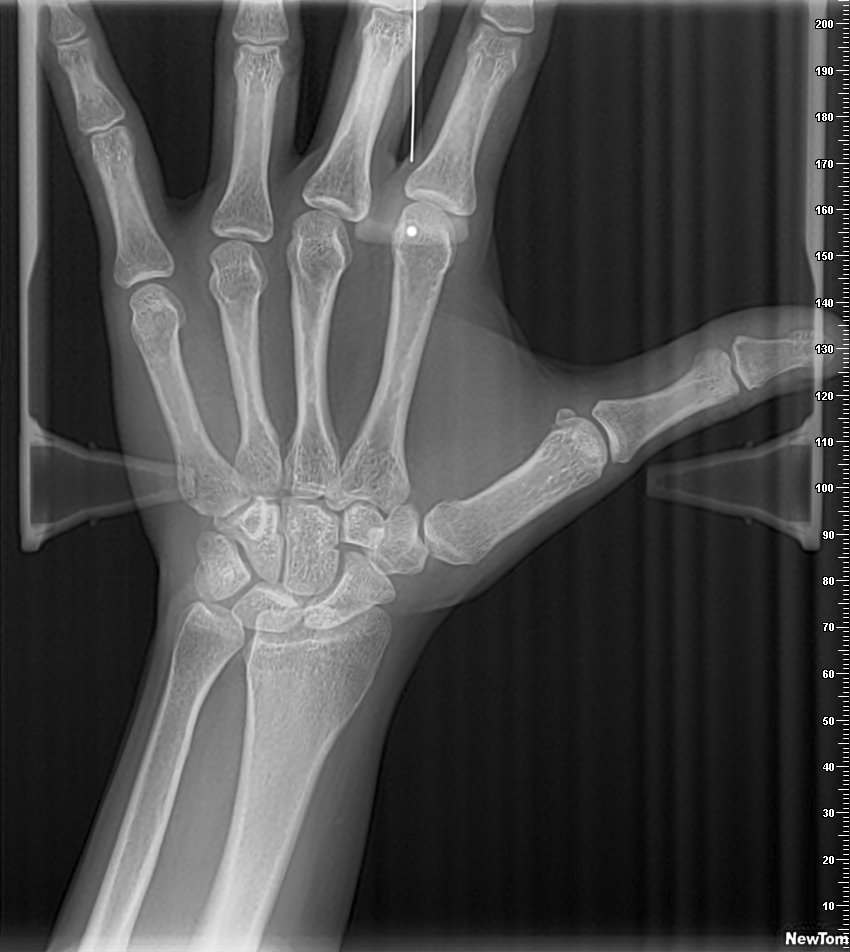

Carpal

La telerradiografía del carpo o radiografía carpal es el método de diagnóstico más usado y aceptado para determinar el nivel de maduración ósea de un individuo. Se utiliza para evaluar la edad ósea del paciente y poder establecer una relación con respecto a su edad cronológica, con el fin de determinar el nivel de desarrollo y maduración. Es importante para la ortodoncia ya que a partir del nivel de maduración se ajusta el tratamiento.v